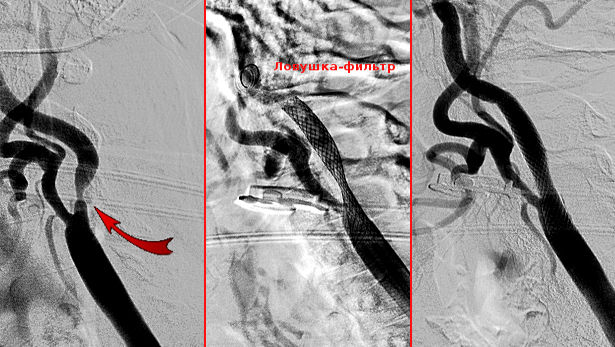

Процедура заключается во введении специального катетера в просвет сосудов, чуть дальше зоны локализации атеросклеротической бляшки. Далее хирург раздувает баллончик, который представляет собой своеобразный зонтик, предохраняющий от смещения тромба дальше по артерии. После этого врач устанавливает стент, который похож на миниатюрную решетку, изготовленную из специального материала.

Через прокол артерии на бедренной артерии катетер подводится к левой или правой сонной артерии. Далее проводится специальное устройство для защиты головного мозга (для профилактики тромбоэмболий) с тонким, хорошо управляемым гибким кончиком за зону сужения, по которому доставляется стент к месту сужения.